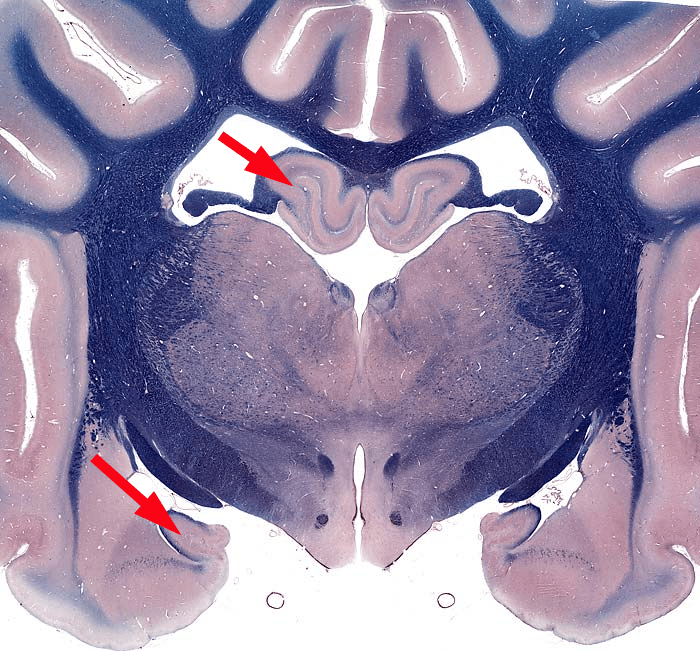

Ippocampo

Le frecce indicano la parte dorsale e ventrale dell’ippocampo, che nel cane ha complessivamente una forma a C con le due estremità libere orientate rostralmente. Quindi su un piano coronale (vedi sopra) se ne osservano entrambe le estremità sezionate (guarda la figura in basso).

Formazione dell’ippocampo

Le differenze di specie nella forma e nell’orientamento dell’ippocampo sono notevoli. Nell’uomo la forma ricorda quella di un cavalluccio marino e da qui è derivato il nome di ippocampo, che riprende quello di alcune creature leggendarie della mitologia greca con testa e parte anteriore del tronco di cavallo e coda di pesce.

L’ippocampo si trova, in genere, profondamente al lobo piriforme dell’encefalo e si incurva dorsalmente e rostralmente.

La formazione dell’ippocampo è situata medialmente al corno temporale del ventricolo laterale. È costituita da subiculum, corno d’Ammone (o ippocampo in senso stretto) e giro dentato. In realtà, nel suo insieme, la formazione dell’ippocampo rappresenta un tipo primitivo di corteccia a tre strati (archicortex) in cui il giro dentato svolge il ruolo che nella neocortex è svolto dal quarto strato. Infatti, il giro dentato è costituito da cellule dei granuli e riceve le connessioni afferenti. Il corno d’Ammone, suddiviso nelle zone CA1, CA2, CA3 e CA4, così come il subiculum, presenta cellule piramidali da cui originano le connessioni in uscita. Dal subiculum origina una sottile striscia di fibre nervose (fimbria) che dà origine al fornice, sistema di fibre per lo più interno al sistema limbico, nel quale si riconoscono le colonne (anteriormente), un corpo e le gambe (posteriormente). La commessura del fornice è il sistema commissurale dell’ippocampo.